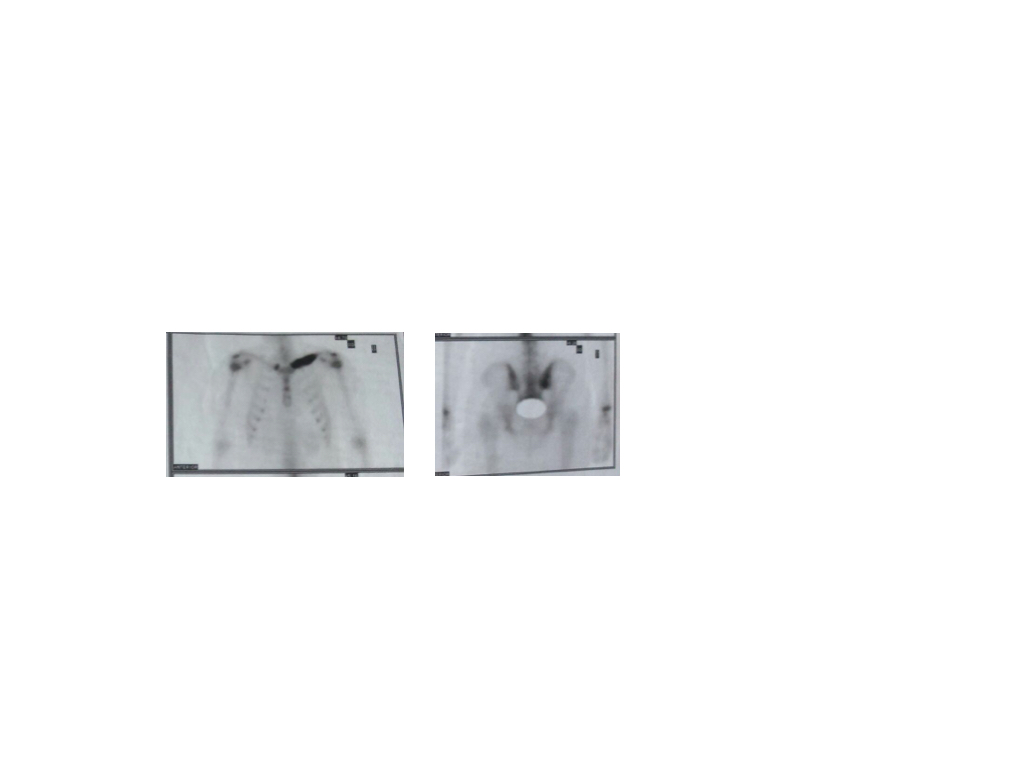

- Centellograma óseo

- Epígrafe de figura 6